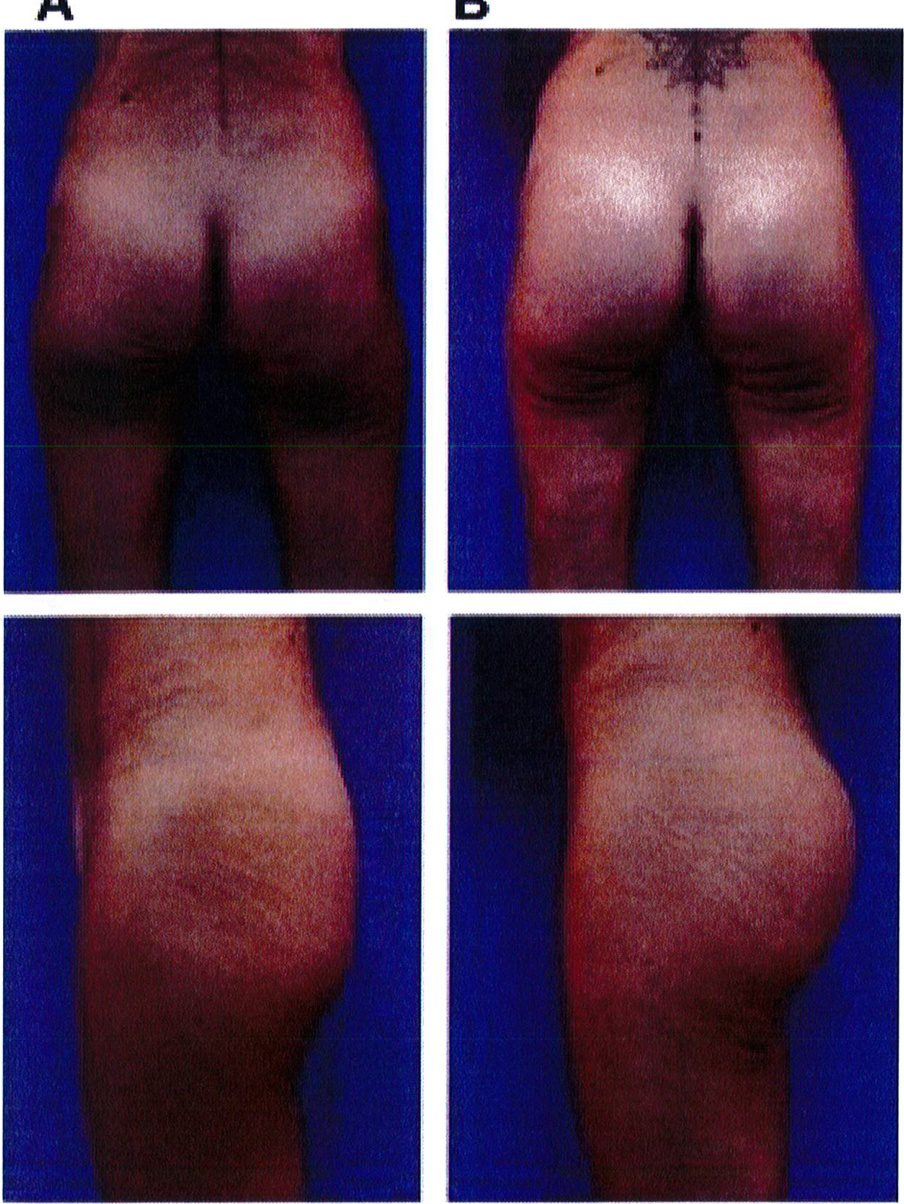

Hình. 18.. (A) Hình anh trước và (B) và sau phẫu thuật làm đầy mông của bệnh nhân được đặt khối implant dưới cân thể tích 225 mL, hai bên.

Hình. 18. (tiếp)

Bệnh nhân 31 tuổi tiền sử khỏe mạnh, có chỉ định nâng mông bằng implant do thiếu hụt thể tích. Hai khối anatomic implant 225 mL polyurethane dạng gel được đặt ở vị trí dưới cân. Sau phẫu thuật không ghi nhận biến chứng trong suốt quá trình hồi phục, vết mổ liền tốt (Hình 18).

Bệnh nhân 52 tuổi xuất hiện chùng da vùng mông (mức độ nặng), mong muốn giải quyết vấn đề này đồng thời tăng kích thước vòng ba. Hai khối anatomic implant

Hình. 19. . (A) Hình anh trước và (B) và sau phẫu thuật làm đầy mông của bệnh nhân chùng da vùng mông tương đối nhiều. Bệnh nhân được đặt khối implant dưới cân thể tích 330 mL ở hai bên.

Hình. 20. (A) Hình anh trước và (B) và sau phẫu thuật làm đầy mông của bệnh nhân có vùng mông tương đối đầy đặn. Bệnh nhân được đặt khối implant dưới cân thể tích 330 mL ở hai bên.